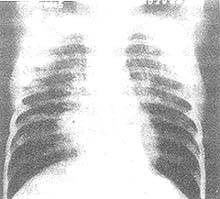

X线形态与病情 病期有密切关系 肺纹理增厚 模糊为腺病毒肺炎的早期表现 肺部实变多在发病第3~5天开始出现 可有大小不等的片状病灶或融合性病灶 以两肺下野及右上肺多见 发病后6~11天 其病灶密度随病情发展而增高 病变也增多 分布较广 互相融合 与大叶肺炎不同之处是 本病的病变不局限于某个肺叶 病变吸收大多数在第8~14天以后 有时若病变继续增多 病情增重 应疑有混合感染 肺气肿颇为多见 早期及极期无明显差异 为双侧弥漫性肺气肿或病灶周围性肺气肿(图1) 1/6病例可有胸膜改变 多在极期出现胸膜反应 或有积液

图1 腺病毒肺炎 肺气肿

3岁 女孩 持续高热咳喘8天 咽拭子分离出Ⅶ型腺病毒 X线胸片显示右肺门增密 两肺内带纹理增厚粗多 右肺内带片状阴影 两下肺透亮度明显增高 两膈位于第10后肋水平 膈面弧度变平 为重度肺气肿表现